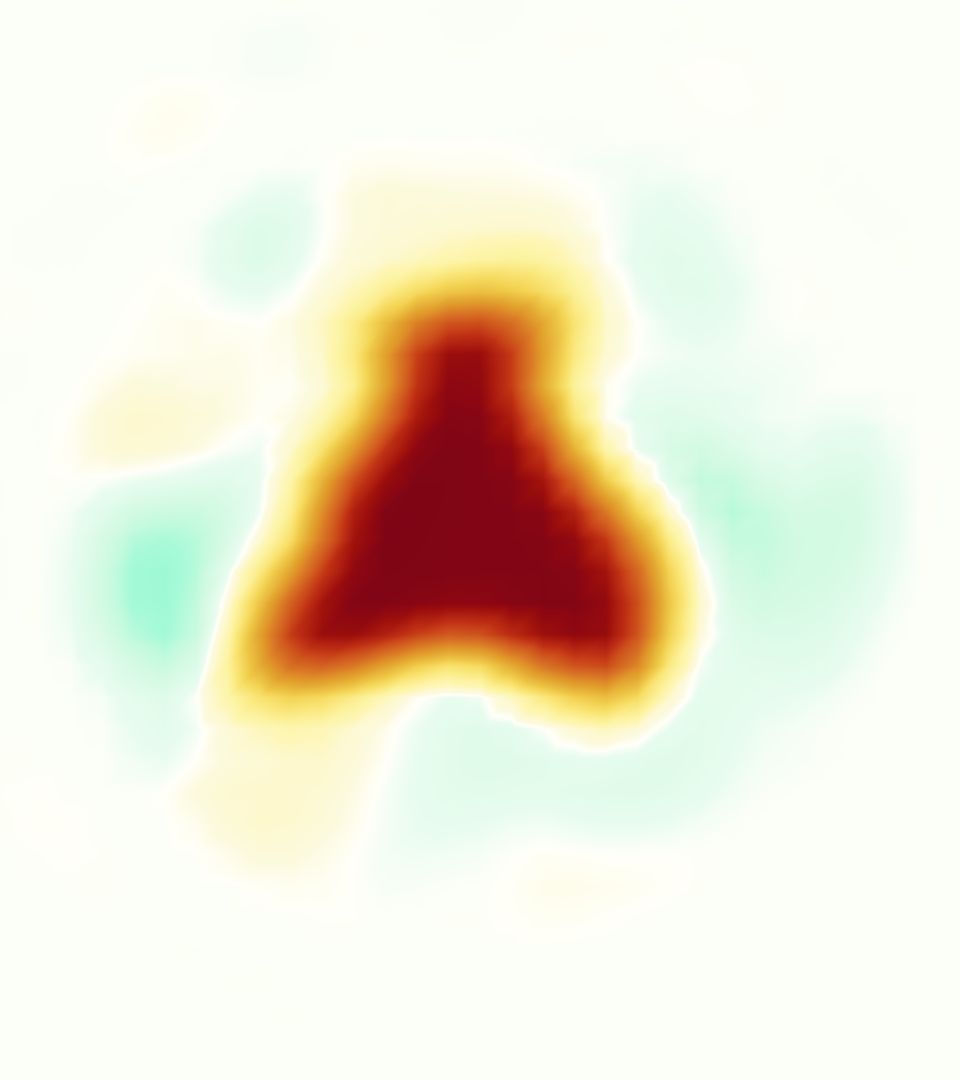

Slice views of the (axial) component of fluid velocity in the axial plane, orthogonal to the flow direction, show that the simulation replicated the development of the jet over the cardiac cycle. At each phase, the simulation matched the forward speed of the core of the jet and the locations of reverse flow back towards the valve annulus. While there are some differences in the shape of the jet at certain phases and locations, the simulation clearly produced the general dynamics of the cardiac cycle that are seen in the experiment.

At = 0, the axial slice directly at the valve annulus shown in columns 1 and 2 in Figure 6, there was excellent agreement between the simulation and experiment over the cardiac cycle in the speed and shape of the jet through the valve. In both cases, the axial velocity increased as the flow accelerated during systole and the valve leaflets opened, then decreased during diastole with slight negative velocity before the valve leaflets were fully closed. The forward flow through the valve annulus did not form a full circle, but rather developed a triangular shape with a point of the triangle forming along the interior curve of the vessel, at the bottom of the axial slices. At = 0, the points of this triangular jet shape aligned with the commissures of the valve. This shape persisted during peak systole and was well-matched by the simulation.

The axial slice = 0.625 cm, shown in columns 3 and 4 in Figure 6, cut through the support scaffolding of the valve and the leaflets when they are open. In the experimental data, the shape of the jet changed as it moved downstream. A triangular shape occurred, but the points were then aligned with the middle of each open leaflet as opposed to the commissures. Those points were also more rounded than they were at = 0. The peak velocity of the jet was faster at = 0.625 cm than at = 0, as the flow accelerated through the open valve leaflets. The simulation produced these features at = 0.625 cm. The triangular shape of the jet shifted similarly, and its speed increased compared to the upstream slice. As the flow decelerated into diastole, the jet shape remained roughly triangular but diminished in intensity before disappearing after valve closure.

The jet continued to develop at = 1.25 cm, an axial slice immediately downstream of the valve scaffolding and open leaflets, shown in columns 5 and 6 in Figure 6. In the experimental data, the points of the triangular jet shape extended further towards the vessel wall. In addition, regions of reversed flow developed in the locations downstream of the commissures, resulting in curved sides to the shape of the jet. Each tip of the jet was unique, due to variations in the individual leaflets in the physical bioprosthetic valve. These variations are apparent in the velocity fields, possibly because the jet edges are similar enough cycle to cycle that irregularities are still being captured even with phase averaging. Further discussion of these features can be found in Schiavone et al. [39], which showed that the jet tip shapes occurred in different pulmonary anatomies, demonstrating that they were likely due to inherent properties of each leaflet. The leaflets in the mathematical model of the valve are identical, so these nuances in leaflet variation could not be replicated. The simulation did capture some of the extension of the tips of the jet, as they were closer to vessel wall at slice = 1.25 cm than = 0.625 cm. The curves in the triangular sides of the jet were also present in the simulation, though they were less pronounced than the experimental data. At both = 0.625 cm and = 1.25 cm, the jet shape in the simulation was smoother than the jet in experiment. It is possible that the free edges of the leaflets in the mathematical model are not fully replicating the behavior of the physical leaflets of the bioprosthetic valve, in particular the amplitude or frequency of leaflet flutter, leading to the variations seen in the jet shape at = 1.25 cm downstream of the leaflet edges. The simulation, however, does capture the key features of the triangular shape and speed of the jet. Overall, qualitative comparisons demonstrated that the simulation reproduced key features of the flow during systole and diastole.